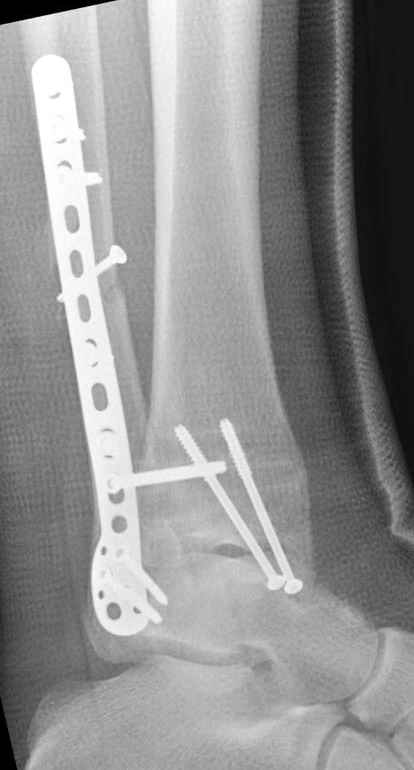

15 ноября прямой

|

15 ноября боковой

15 ноября трехчетвертной

12 января прямой

12 января боковой

12 января трехчетвертной

Вариант с артродезом уже обсудили. Хотя, после увиденых снимков, пессимизм насчет восстановительной операции у меня, например, несколько уменьшился. Особенного уж какого-то остеопороза не видно даже на январских снимках. Можно черед мини-доступы убрать винты, аппаратом вправить малоберцовую кость, устранить подвывих стопы. Ну а дальше фиксировать малоберцовую пластиной сзади. А может, и напряженной Y-спицей попробовать - Анатолий Федорович, как Вы полагаете? Внутреннюю - то, что осталось, если уже не получится сделать спицами и проволокой, то что-то типа пластики дельтовидной связки. А может, и не трогать ее вовсе... В общем, выбор непростой,

много факторов надо взвесить.

Если до сих ничего не сделано, с артродезом сустава в данный момент я бы повременил, на выставленных январских снимках хорошо сохранившийся сустав, а в "мортиз" (трехчетвертной) и на боковых снимках не менее 5 мм укорочение малоберцовой кости. Косые переломы лучше фиксировать пластинами, как то мы разбирали случай, где было отмечено, что это закон "таранная кость всегда следует за малоберцовой".

В данном случаи я бы уговорил больного на реконструкцию, для этого после удаления шурупов, спереди очистить от рубцов синдесмоз, несросшуюся наружную лодыжку - остеотомия по линии перелома и компрессирующий (lagging technique) кортикальный шуруп 3.5 мм по поперечнику остеотомии. Следующий этап - восстановление длины малоберцовой за счет удлинения, сделать поперечную остеотомию где-то на уровне сантиметр выше вашего синдесмозного шурупа, наложить длинную пластинку, прикрепить пластину за дистальный конец двумя или тремя шурупами; сохраняя контакт пластины с костью, имеющимся

compression&tension device AO system (при отсутствии любой lamina spreader подойдет, создать дистанцию между пластиной и шурупом, проведенным проксимальнее пластины) толкая проксимальный отдел пластины, низвести пластину, мортиз рентгенограмма подскажет на сколько. Если заранее сделать предоперационный план (ренгенограмма другой стороны), тогда точно можно определить, на сколько вам необходимо сделать поперечную остеотомию малоберцовой кости, для закрытия создавшегося дефекта.